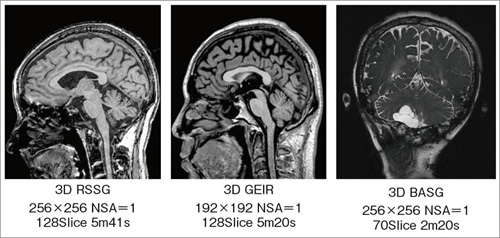

次世代のOpen Bore 3T MRIによる臨床応用 3T MRIの臨床応用。Look back Gyro cup ②「 CSF Flow with Low RFA SSTSE。次世代のOpen Bore 3T MRIによる臨床応用 3T MRIの臨床応用。